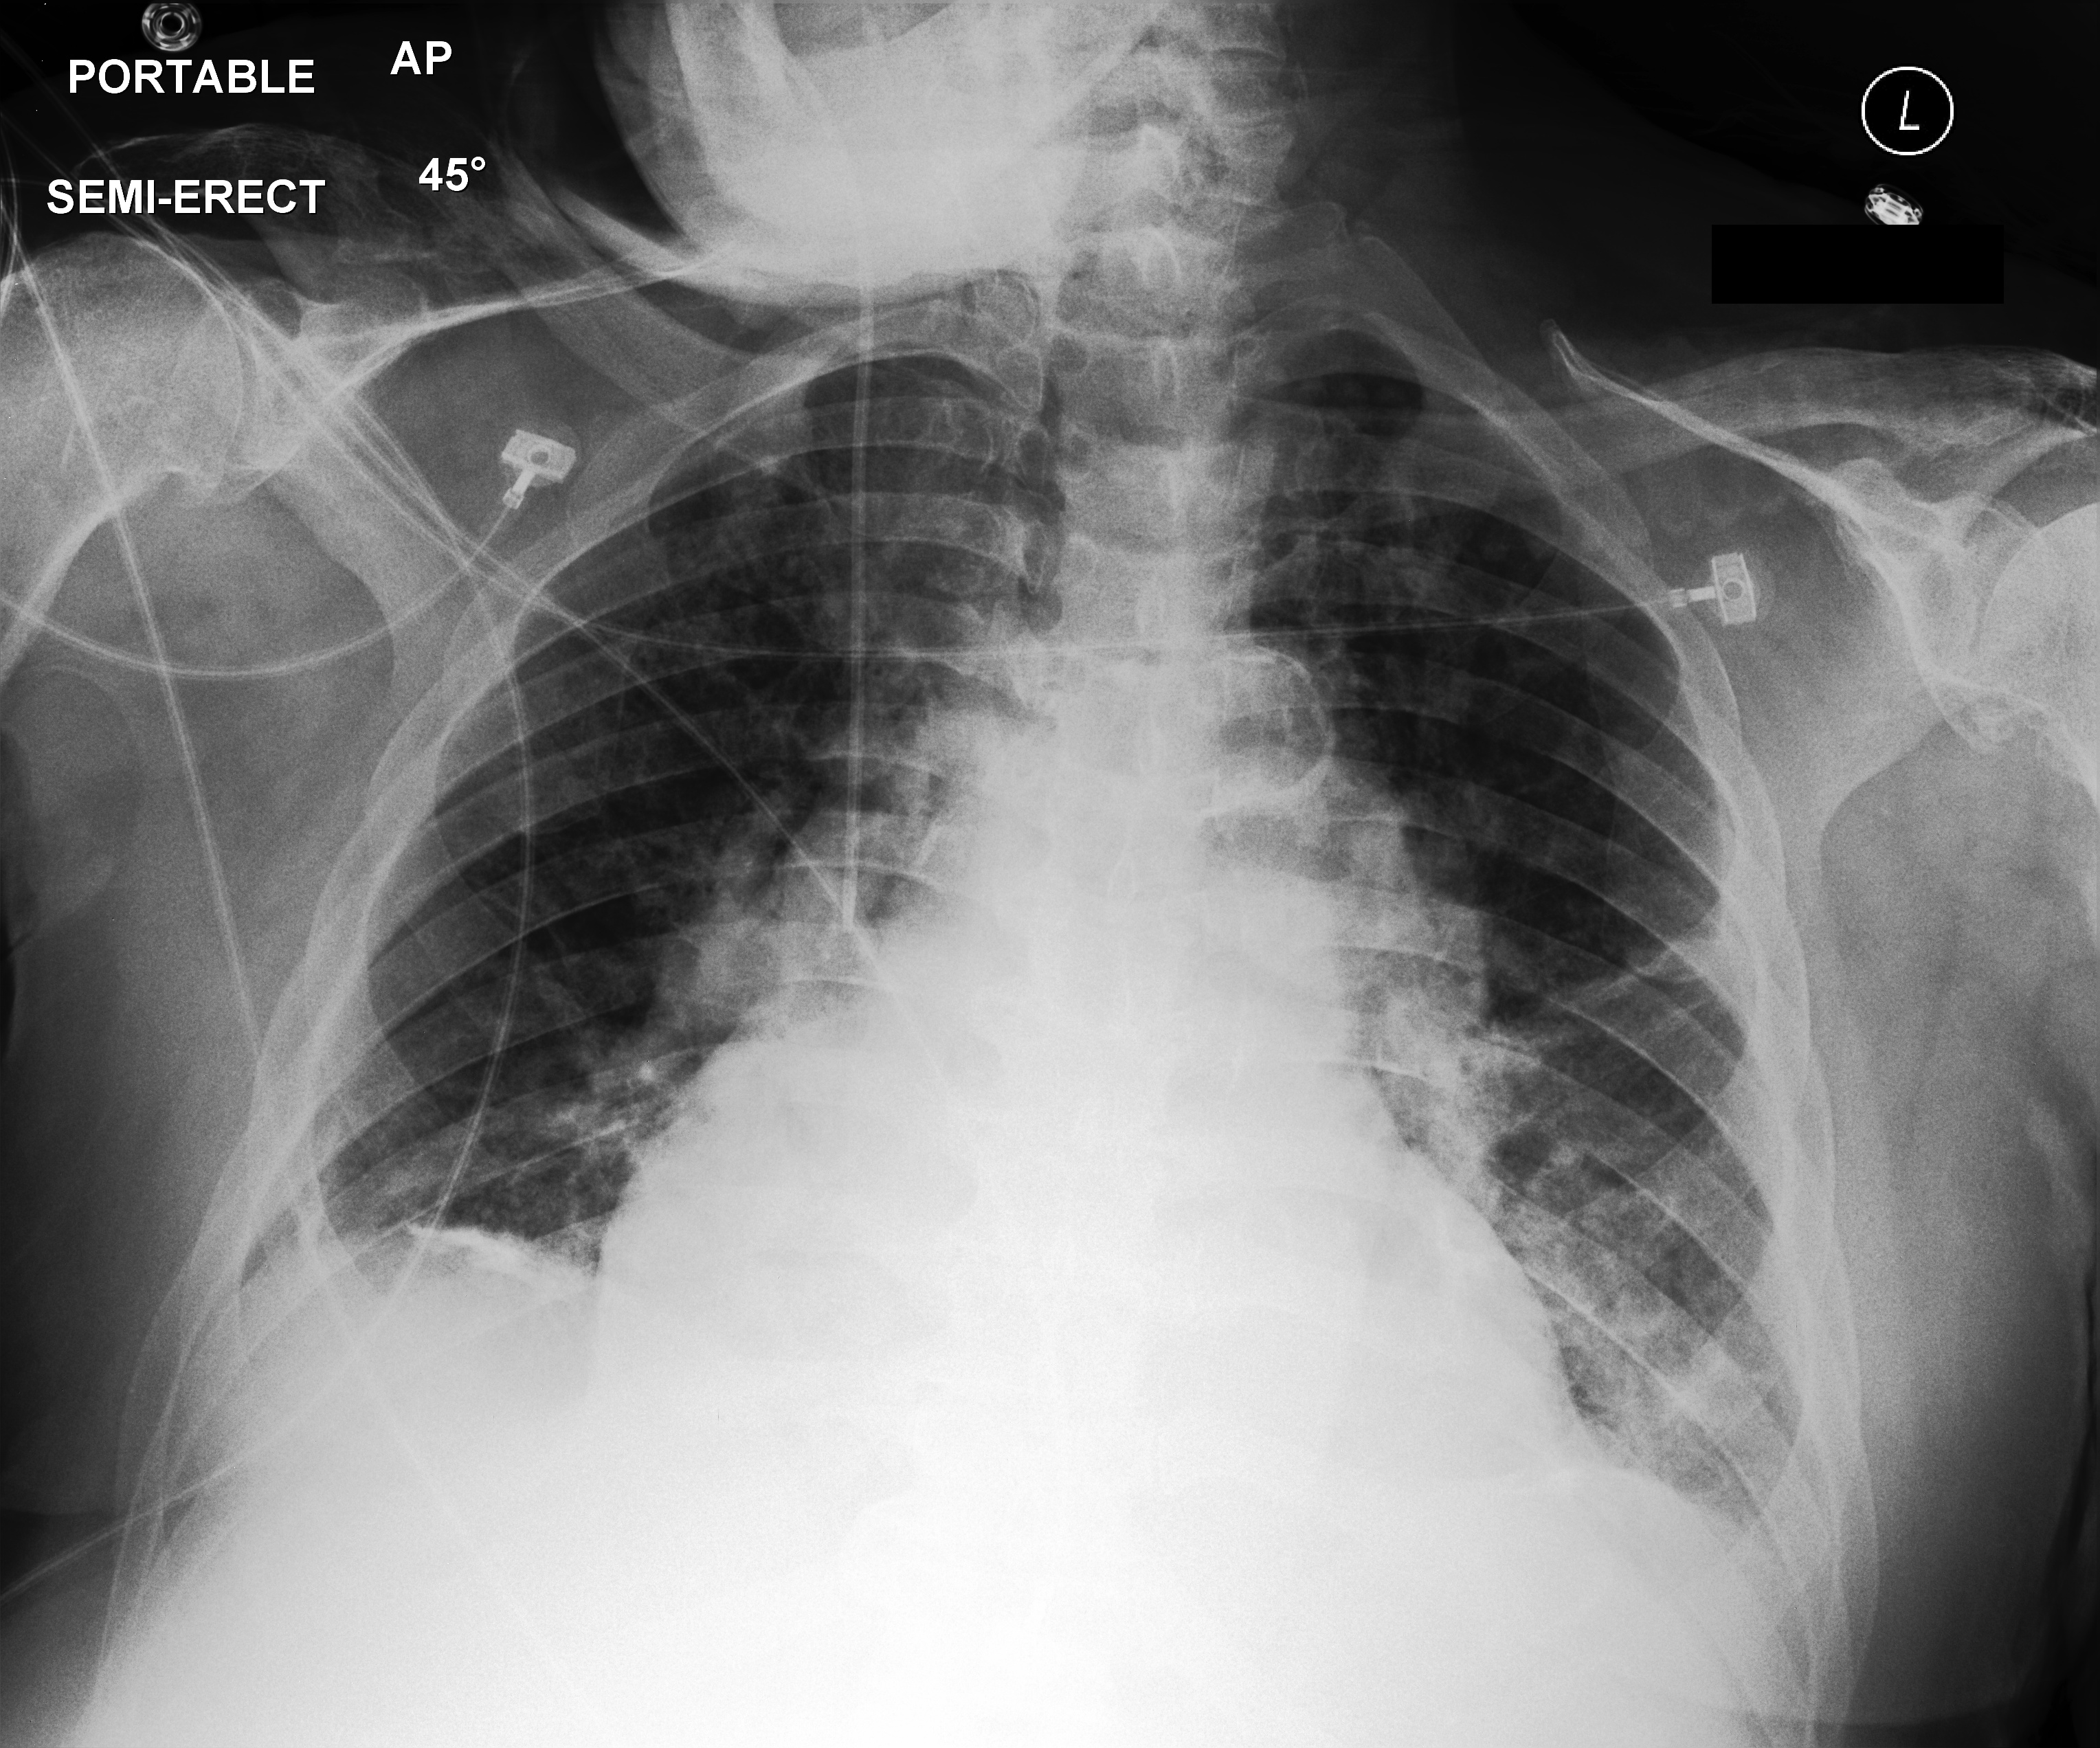

4.3.4 Conversational abilities

Our model can already handle multiple advanced tasks for CXR interpretation. However, we have only tested its ability to follow instructions in a single-turn, question-answer format so far. An essential aspect of a VLM’s performance is also its capacity to manage follow-up questions in a multi-turn exchange with the user. Simply generating a full report or marking image features in one shot does not necessarily imply that the model can handle a varied sequence of precise questions – covering observations, locations, clarifications of medical terms, and more.

RadVLM’s instruction dataset also includes image-conversation pairs (Figure 2) generated with GPT-4o, by providing it with a radiology report, any available grounded phrases, and additional details. As mentioned in Section 4.1.4, we created two held-out evaluation sets using GPT-4o: one without grounded questions and one focused on grounded questions derived from the MS-CXR test set (Table 1). We run the evaluation on both test sets and report the average score across all samples. We also evaluate the other baseline models that possess conversational abilities, thoroughly respecting their prompting template within a multi-turn setting. The average GPT-4o scores for RadVLM and other models are gathered in Table 5.

Our results show that RadVLM, trained on a broad range of image-conversation pairs, achieves an average score of 6.66/10, substantially higher than the other conversational models, whose responses often prove incorrect or vague (Figure 6). This advantage may stem from RadVLM’s ability to handle varied question types and sequences in multi-turn exchanges, a skill reinforced by the sparse nature of its training conversations. The gap becomes even more pronounced in grounded scenarios, where RadVLM maintains strong performance (6.60/10) while others drop even more. Notably, this suggests that even the limited number of grounded conversations included (Table 1) was sufficient to equip RadVLM with robust grounding capabilities in a multi-turn setting.

| Model | GPT-4o Score | GPT-4o Score w/ grounding |

| LLaVA-OV | 3.66 | 2.95 |

| LLaVA-Med | 3.52 | 2.95 |

| RaDialog | 3.62 | 3.11 |

| RadVLM | 6.66 | 6.60 |